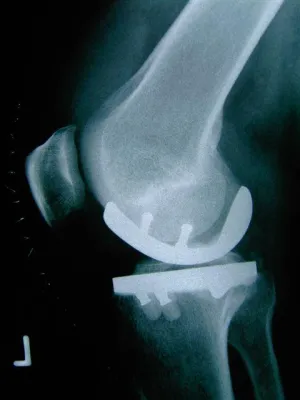

(openPR) Seit nun gut über einem Jahr wird im Zentrum in der Münchener Clinic-Dr-Decker eine Knieprothese implantiert, die auch für besonders schlanke Gelenke gedacht ist, wie es z.B. bei Frauen sehr häufig vorkommt. Sehr gute Ergebnisse zeugen davon, dass diese Vorgehensweise richtig ist.

Bei dem "Frauenknie" handelt es sich nicht, wie fälschlicherweise in vielen Pressemitteilungen erwähnt, um eine Prothese, die nur für Frauen konstruiert wurde, sondern um eine Prothese mit vielen Zwischengrößen, u.a. ideal für sehr schlanke Knochen. Sehr oft muss dieser Prothesentyp auch bei Männern implantiert werden.

Bei einer insgesamten Erfahrung von über 3500 Knieprothesen und -teilprothesen hat sich herauskristalisiert, dass man als Operateur sehr flexibel sein muss, um sich an verschiedene Gegebenheiten anzupassen. Wichtig bei der Planung eines Eingriffes ist nicht nur die richtige Diagnose, sondern auch die möglichst große Auswahl von Implantaten im Hintergrund zu haben. So kommt es vor, dass manche Firmen Prothesen in nur 3 oder 4 Größen anbieten. Keine Zwischengrößen, so wie es viele schlanke Knie benötigen, sind vorhanden. Aus diesem Grunde muss man oft einen Kompromiss zwischen Höhe und Breite eingehen.

Besser ist es also, wenn man mehr Möglichkeiten anbieten kann. Wir hingegen haben jeweils 7 unterschiedliche Größen pro Knie zur Auswahl und können uns so jeder Situation anpassen.

Bevor ein künstliches Gelenk eingebaut wird, hat man intraoperativ noch viele Möglichkeiten auszutesten, welche der vorhandenen Größen wirklich optimal passt. Erst dann wird das definitive Implantat ausgewählt- je nach Knochenqualität - einzementiert oder passgenau eingeschlagen. Auch wir versogen die Knieprothesen minimalinvasiv, dass heißt mit möglichst kleinen Hautschnitten. Eine große Auswahl von Implantaten sind immer vorrätig, so dass man sich an jede individuelle Sitaution anpassen und auf mögliche Probleme reagieren kann, ohne eine OP verschieben zu müssen.

Wichtig scheint es mir hier zu erwähnen, dass es auch Knieprobleme gibt, die sich nur auf einen Teildes Gelenkes beschränken (meistens medial oder innen). Oft sieht man dies Erkrankung auch nur hinter der Kniescheibe (Retropatellararthrose). Hier werden wir nie eine ganze Prothese einbauen, sonderndas betroffene Areal nur mit einer Teilprothese überkronen!